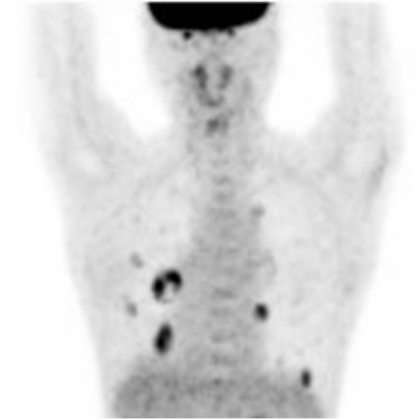

治療前のPETで黒くみられる両肺に多発する転移性肺がんの多くは、計3回のラジオ波治療後のPETで消失しています。このようにラジオ波治療は繰り返して行うことができ、多発する病変の治療も可能です。